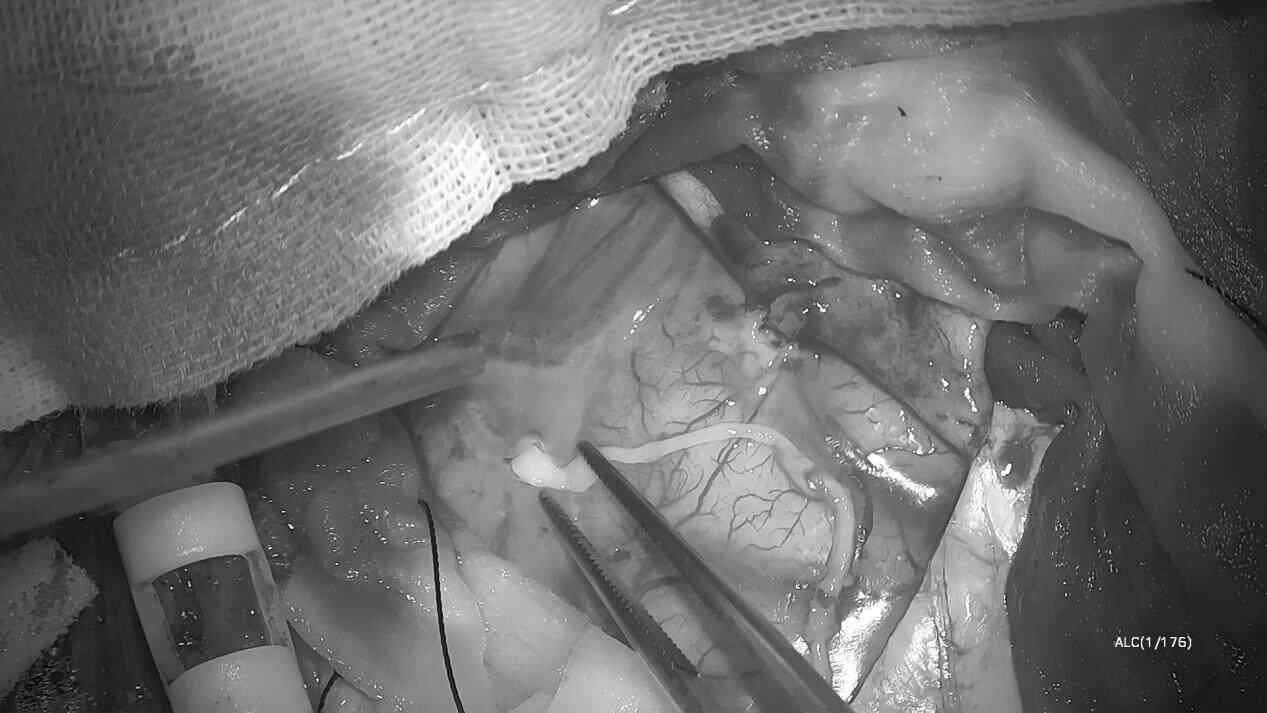

手术当天,医护团队先在全麻状态下完成开颅。当暴露病灶区域时,麻醉科医生逐步调整用药,将林浩从麻醉中唤醒,“能听见我说话吗?试着睁睁眼。”林浩根据指令吐舌、握拳、回答简单问题……通过实时互动,张旭标精准定位功能区边界,并成功捕获一条约10厘米长、仍在蠕动的裂头蚴。